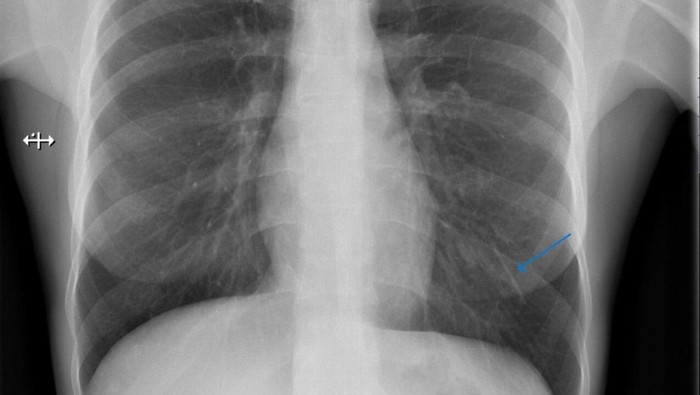

Dari sana, implan itu berjalan ke jantungnya, sebelum dibawa melalui arteri ke paru-paru kiri bawahnya.

Faktor risiko lain untuk migrasi implan termasuk memasukkan implan terlalu dalam ke dalam jaringan di lengan pasien yang sangat tipis. Jika implan berhasil sampai ke paru-paru, kejadian itu dapat menyebabkan berbagai gejala, seperti batuk yang bisa berdarah, sesak napas atau nyeri dada. Jika implan yang berkeliaran masih aktif, maka pasien mungkin memerlukan operasi untuk menghindari potensi efek samping seperti infertilitas dan masalah menstruasi.

Dokter juga mencatat bahwa implan tidak bergerak setelah konsultasi lanjutan enam bulan kemudian. Karena implan tidak lagi melepaskan progestin, wanita itu memilih untuk tidak menjalani operasi untuk mengeluarkannya.